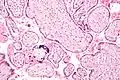

- Placentitis por citomegalovirus (CMV)